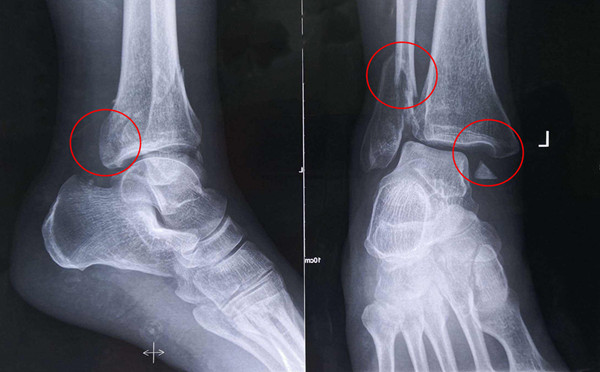

踝關(guān)節(jié)骨折在X影像上的表現(xiàn)有很多種。如內(nèi)踝骨折和外踝骨折,我們可以在影像上看到骨折處的骨折線是不連續(xù)的。還有后踝的骨折,內(nèi)踝、外踝、后踝聯(lián)合在一起發(fā)生的骨折,我們稱之為“三踝骨折”,這些都是在X影像上能夠顯示出來的。

內(nèi)踝骨折

外踝骨折

后踝骨折